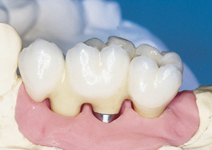

Protetické řešení může být pomocí můstku, který je kotvený na implantátech nebo pomocí jednotlivých korunek na implantátech.

V zásadě je možné do těchto můstků zařadit i přirozené zuby, zejména pokud je potřeba tyto zuby ošetřit proteticky - korunkami. Korunky nebo můstky mohou být na implantáty nacementovány nebo přišroubovány.

Zdravé zuby zůstanou zachovány a přitom náhrady jsou pevné, jako na vlastních zubech